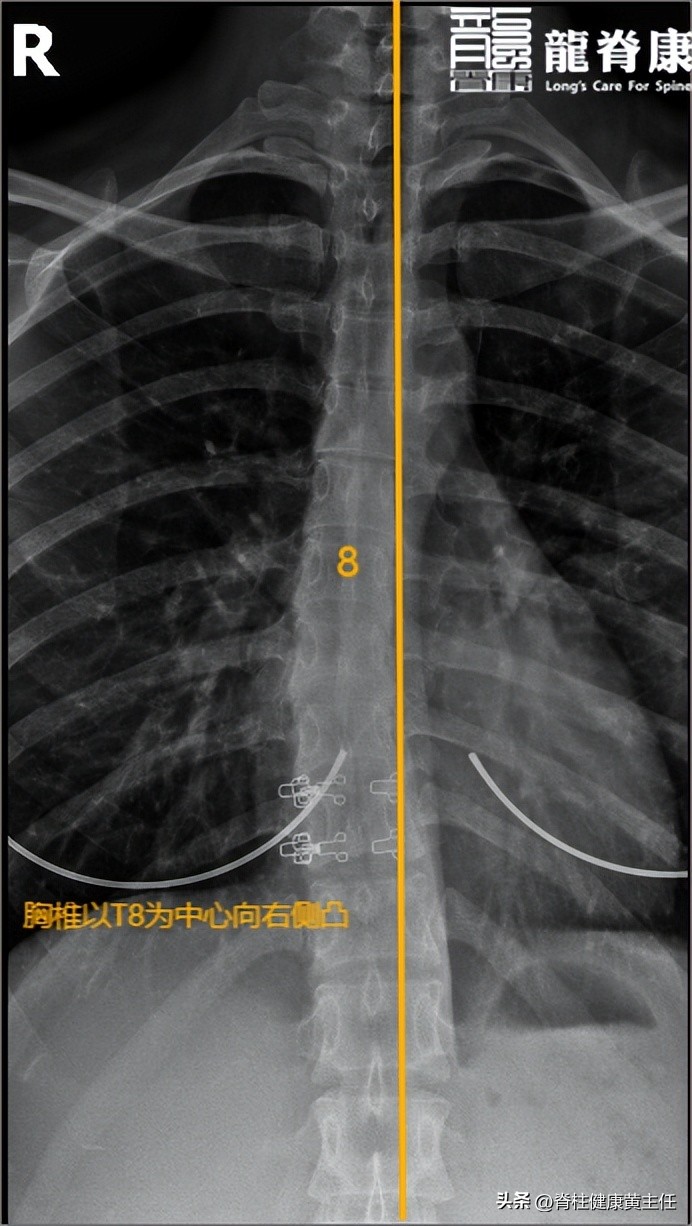

颈椎寰齿间隙不等宽,右宽左窄;颈椎多个棘突偏右,颈椎生理曲度变直;胸椎以T8为中心向右侧凸;腰椎多个棘突偏右。

胸椎正位片